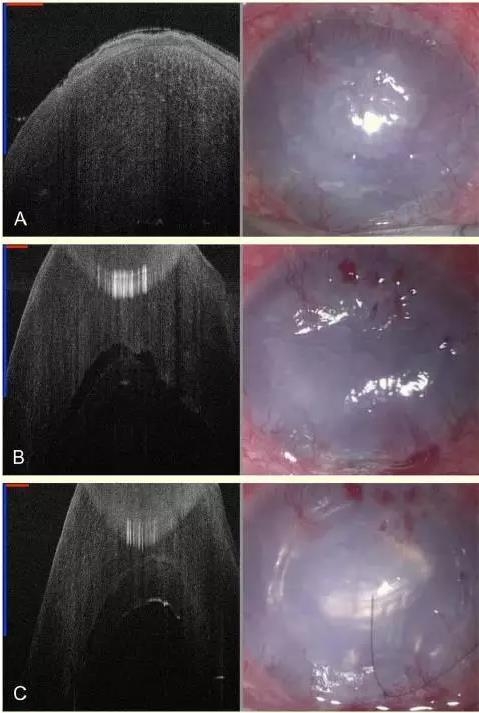

患者女性,86 岁,左眼曾植入后房型人工晶状体。现左眼因严重的角膜失代偿视力仅有手动,裂隙灯下可见角膜水肿和大泡,无法透过角膜窥清前房,但是术前 SD-MIOCT 可清晰显示角膜水肿程度(图 1-A)。考虑到患者年龄以及曾因急性青光眼发作行房角分离术和周边虹膜激光切开术的病史,因此采用 DSAEK 代替传统的 PK 缓解患者的疼痛症状,改善视力。

经角膜切口剥除后弹力层后,可先用 MIOCT 观察角膜后是否有残余的后弹力层碎片。植入内皮移植物时,常规手术显微镜已无法看清,通过术中 MIOCT 可以精确看到移植物和患者角膜之间的位置关系(图 1-B)。注入填充空气后,在 MIOCT 下通过与填充空气显影的对比,可以看清移植物的边缘(图 1-C)。

图 1 左为 SD-MIOCT 2D B-scan 图像,右为显微镜下所见角膜;A 为术前严重的角膜水肿;B 显示了角膜内皮移植物与患者角膜的关系;C 为注入填充空气后移植物与角膜基质贴附;D 为完成移植手术后的角膜(图中用红、蓝线段长度表示 1 mm)